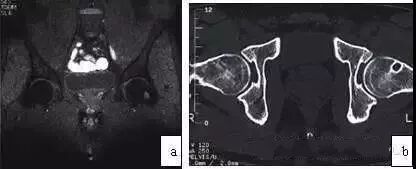

典型ONFH的MRI表现为T1WI低信号带包绕脂肪信号,T2WI出现双线征(double line sign),T2WI抑脂像或STIR序列出现片状或带状高信号(图1),此异常信号改变多数位于闭合的骨骺线以近,但部分ONFH的坏死信号带可穿透骨骺线至股骨头远端,少数可穿透股骨颈部。约20%的ONFH不出现T2WI的双线征。如在股骨头颈及转子部出现骨髓水肿,提示坏死病灶进展到围塌陷期。

图1 典型的股骨头坏死MRI图像(a)T1WI带状低信号;(b)T2WI双线征;(c)T2WI抑脂像示带状高信号